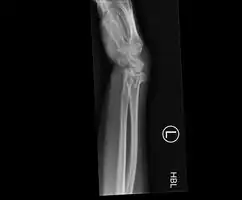

Bilateral Colles fractures/frontal

Bilateral Colles fractures/lateral